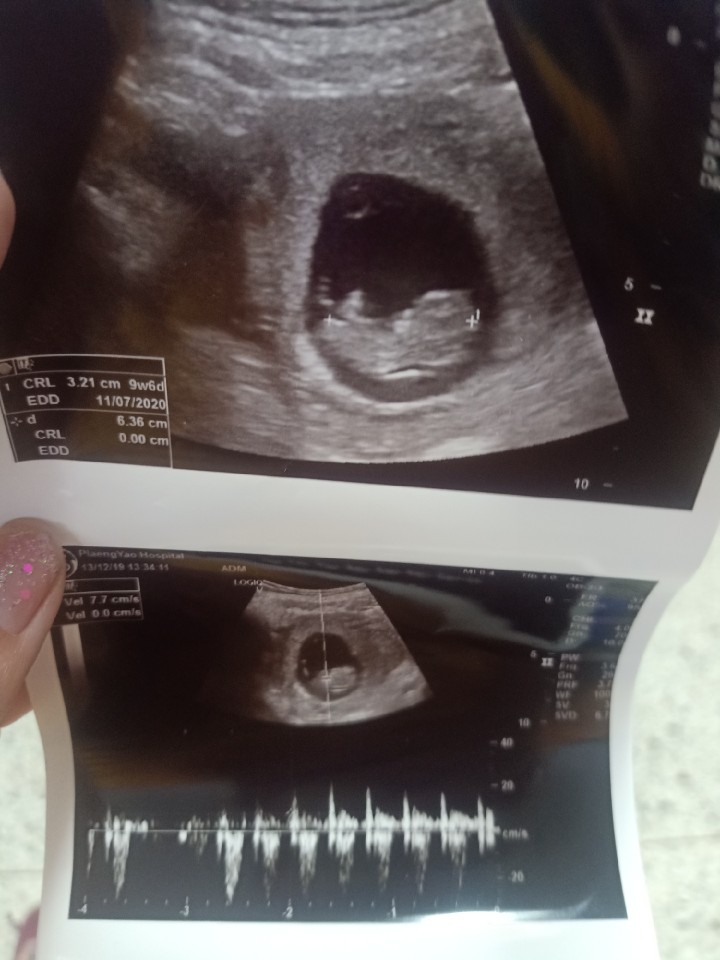

ไปซาวมาเมื่อวาน 10w4d